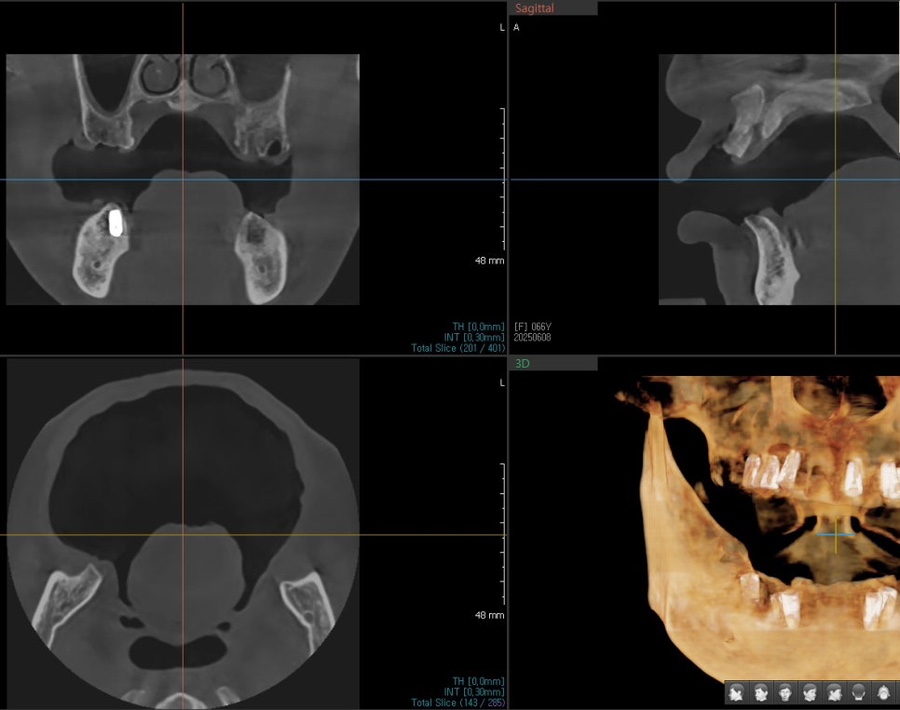

Detailed diagnosis

At our Jamsil dental clinic, Seoul OB Dental Hospital,

even senior patients are carefully assessed for their current dental condition

through a 3D scanner, intraoral endoscopy, and bite examination.

The examination showed that

enough tooth structure remained in the front teeth,

so veneers could be done without excessive reduction,

and the gum condition was also stable.

The bite was also well aligned without any major issues,

so this was a case in which improving only the color and shape of the existing prosthetics

could restore a more natural and balanced front tooth line.